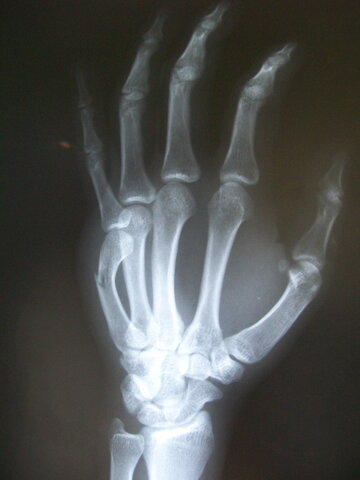

• Fractured my left hand

Fractured my left hand

I fractured my ring finger and pinky finger on my left hand because a little boy ran into my hand.